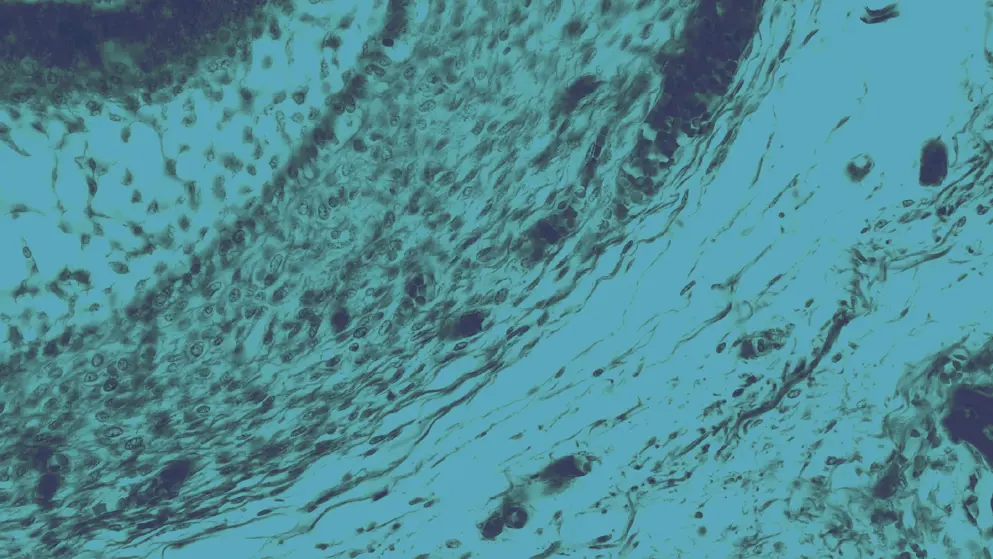

retina, cell image, blue overlay

Retinal dystrophy encompasses a wide range of heritable, progressive, and degenerative eye disorders that are associated with poor or deteriorating vision1. In retinal dystrophy, damage, or loss of function of photoreceptor cells of the retina (rod cells and cone cells) impact on the processing of sight information by the brain. Inherited retinal dystrophy symptoms may first present from infancy through to adulthood, depending on the defect. Symptoms similarly vary but commonly include loss of night vision (night blindness), reduced field of vision including tunnel vision, blind spots, and loss of central vision and visual acuity1.